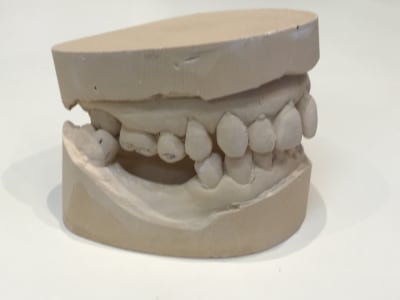

D autant plus que ce n est pas un wax up ça , mais du coloriage blanc .

> D autant plus que ce n est pas un wax up ça , mais du coloriage blanc .

Pcq le probleme de ce cas est , entre autre , un decentrage lateral du au couple 17/ 47 .

Or il n a pas touché la 47 .

Donc ça ne sert à rien :-)

De + ,Les centrales du haut ,se sont decalées

Or il ne les a meme pas taillees , mais rempli les espaces .

Donc ça ne sert à rien .

A tout les coups il n y a pas eu de centree ( pour cela il aurait fallut limer la 47 ) .

Donc ça ne sert à rien

Le wax up n a d interet que pour proposer 1 nouvelle occlusion , pas pour embellir des faces vestibulaire ,en ayant ouvert la tige incisive .